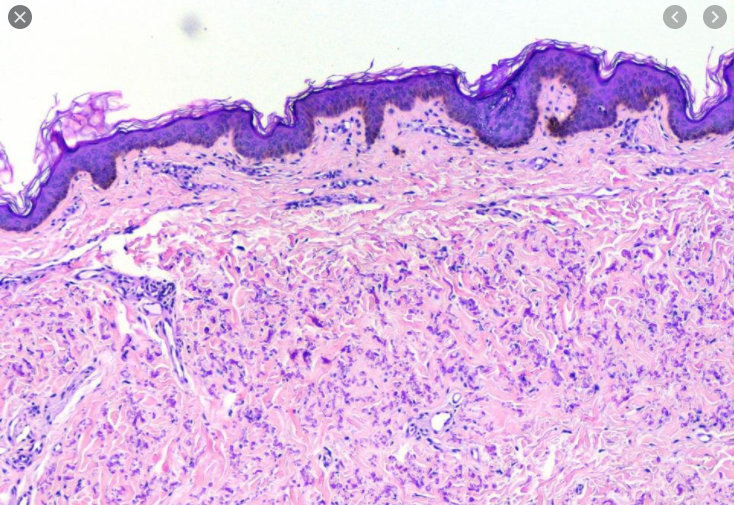

Relatively normal looking biopsy but diminished granular layer and compact hyperorthokeratosis

Ichthyosis Vulgaris

Normally if there is hyperkeratosis the granular layer will be thick or if there is parakeratosis the granular layer will be absent. In this there will be hyperkeratosis without a granular layer which is odd.